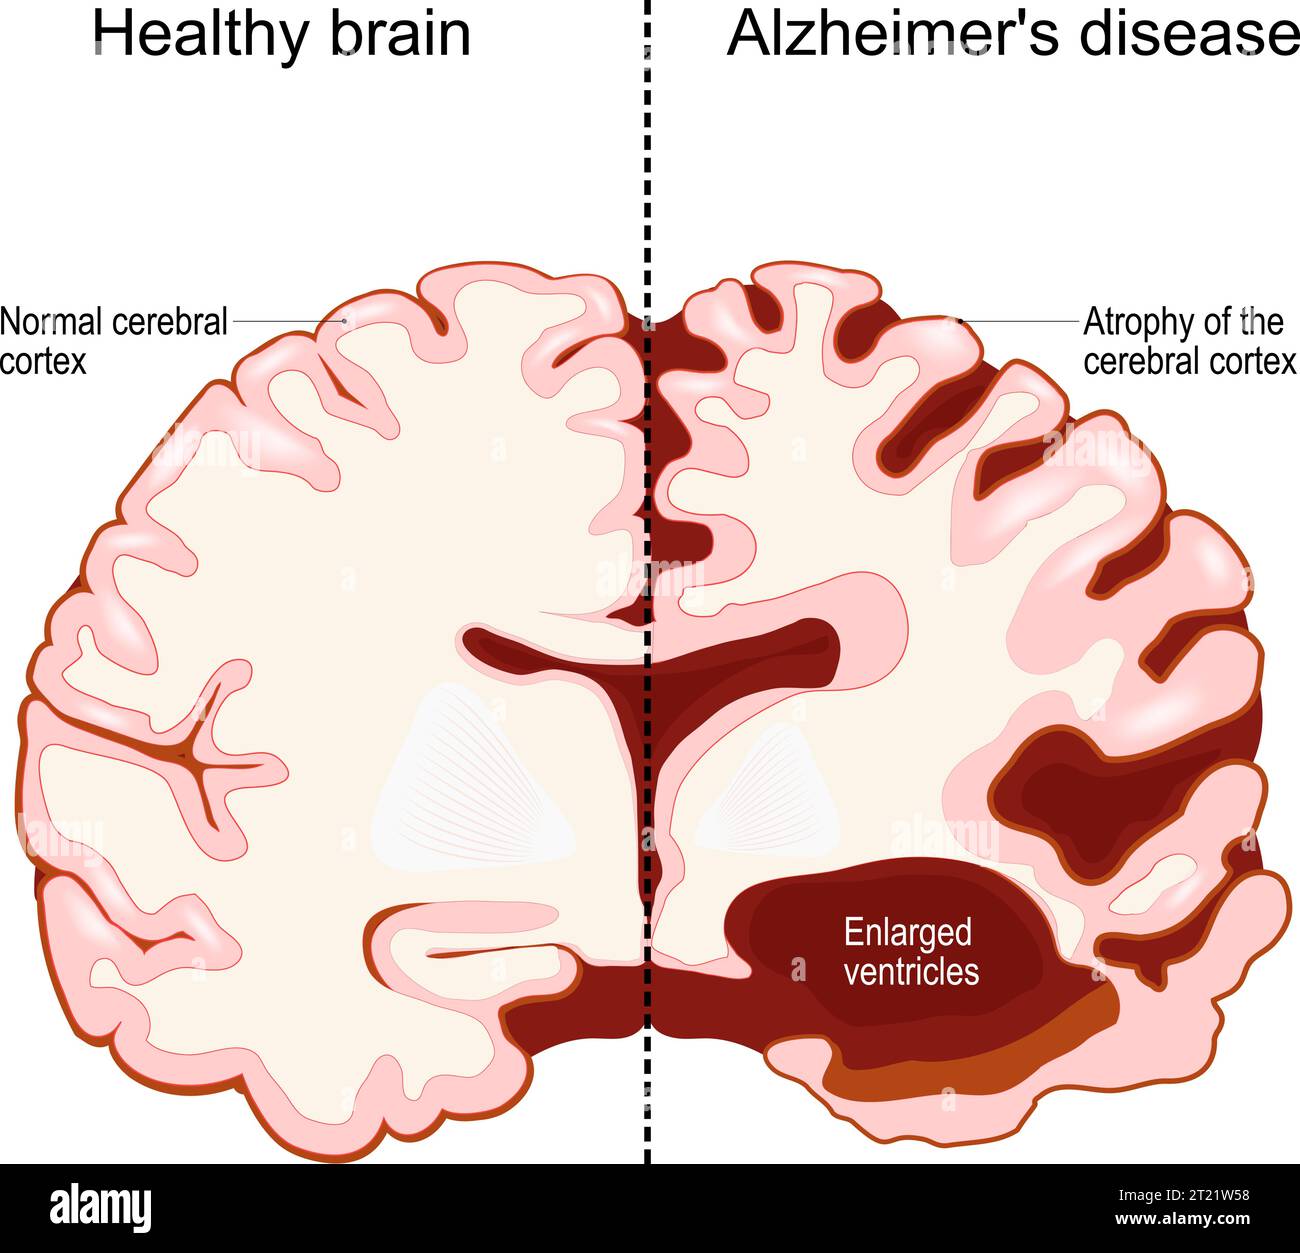

RF2XARW8C–Morbo di Alzheimer. Neurodegenerazione. Sezione trasversale del cervello normale e Alzheimer, con atrofia della corteccia cerebrale, ventricoli ingrossati e Hipp

RF3BH7B1F–Morbo di Alzheimer. Neurodegenerazione. Sezione trasversale del cervello di Alzheimer, con atrofia della corteccia cerebrale, ventricoli ingrossati e ippocampo. Un

RF2T21W58–Cervello umano, in due metà: Sano e morbo di Alzheimer. Disturbo neurodegenerativo. Demenza. Perdita di memoria e declino cognitivo. Sezione trasversale di

RF2FM2W9M–L'Alzheimer, è una malattia neurodegenerativa. Demenza. Confronto e differenza tra cervello sano, morbo di Alzheimer grave e cognitivo lieve